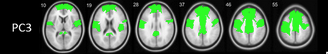

Recent work using 18F-FEOBV PET with our colleagues in Michigan Medicine #neurology reveals a specific topographic pattern of regional vulnerability of cholinergic nerve terminals across multiple cholinergic systems in normal aging. Out now in #AgingBrain: sciencedirect.com/science/articl…